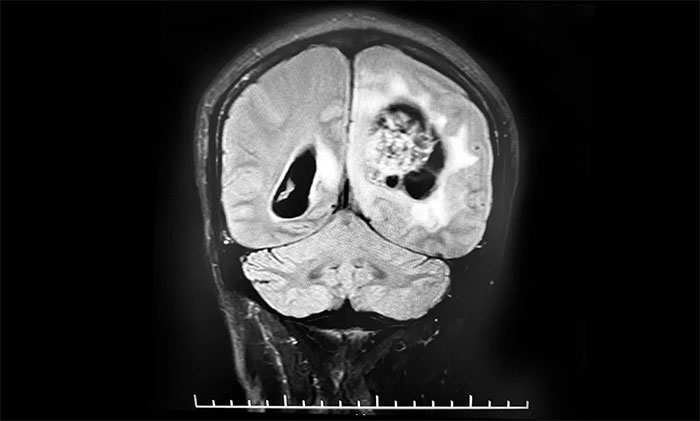

頭顱MRI平掃+增強+DWI+MRA提示,左側頂枕葉巨大腫瘤伴局部瘤卒中,幕上腦室系統、腦幹受壓變形,中線結構右移19mm,大腦鐮下疝形成。李士其教授等專家團隊會診指出,患者腦內巨大佔位,性質不明,並且患者已經發生腦疝昏迷,生命危在旦夕,應儘快進行手術治療,挽救患者生命,同時明確病理診斷。

▲ 左側頂枕葉巨大腫瘤伴局部瘤卒中